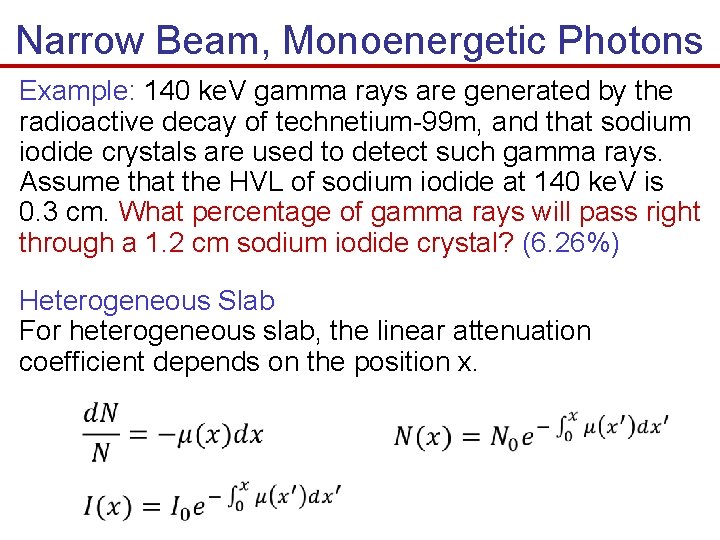

Narrow Beam, Monoenergetic Photons Example: 140 ke. V gamma rays are generated by the radioactive decay of technetium-99 m, and that sodium iodide crystals are used to detect such gamma rays. Assume that the HVL of sodium iodide at 140 ke. V is 0. 3 cm. What percentage of gamma rays will pass right through a 1. 2 cm sodium iodide crystal? (6. 26%) Heterogeneous Slab For heterogeneous slab, the linear attenuation coefficient depends on the position x.